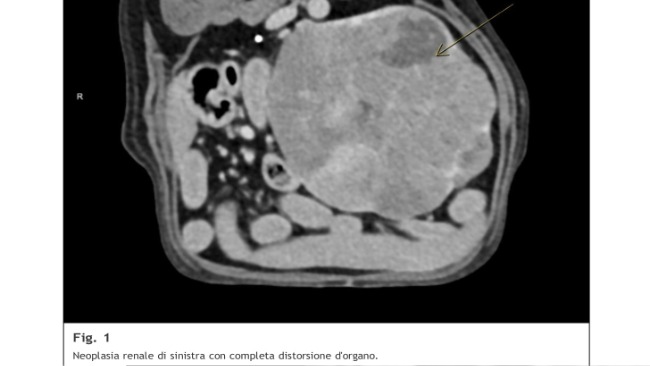

Tłumaczenie podpisu zdjęcia z tomografu: Nowotwór lewej nerki z całkowitym zniekształceniem narządu.